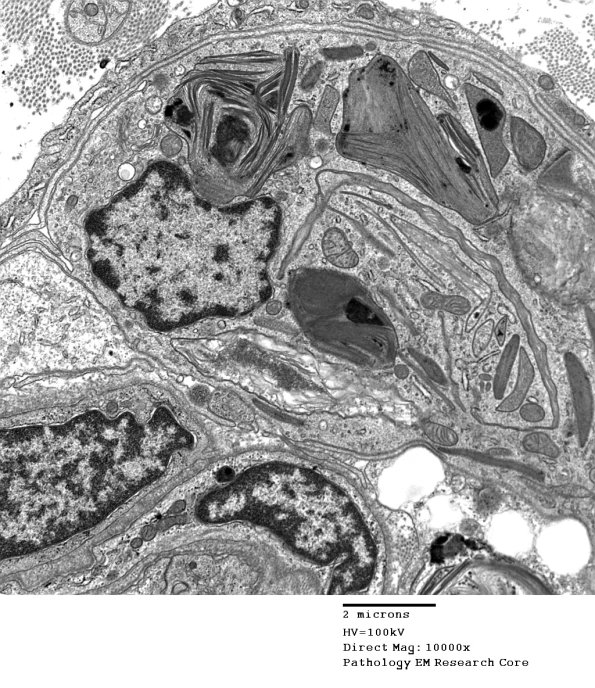

4L2 Axonal Degeneration (Case 4) EM 070 - Copy

Higher magnification of image #4L1. (electron micrograph)